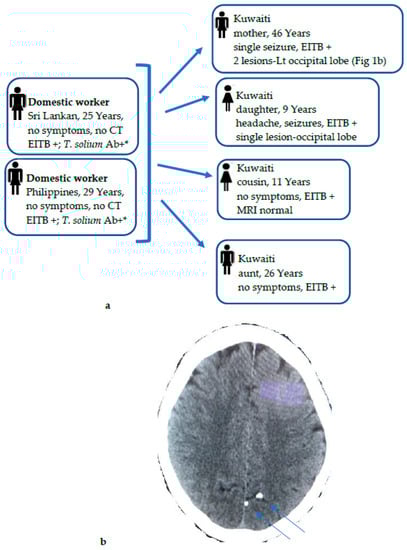

NCC cases (n = 52) among Kuwaiti nationals were detected among individuals who had never consumed pork, and most of them had also not travelled to any of the countries in which T. solium infection is endemic. Kuwaiti people generally like to consume a lot of meat (chicken, lamb, beef, camel, and seafood), dairy products, and sweet dishes. Pork farming is strictly prohibited, and pork is not consumed at all due to the Islamic culture. The total population of Kuwait in 2019 included ~1.3 million citizens who employed >650,000 domestic workers and babysitters mainly originating from India, Sri Lanka, Nepal, the Philippines, and Ethiopia, which are endemic for T. solium taeniasis [,,,] and could, therefore, pose a possible risk of infection transmission to the local Kuwaiti population through the fecal–oral route. This is also supported by a recent study that screened 500 newly arrived domestic workers and found 4.8% of these workers to have high levels of anti-T. solium taeniasis-specific IgG antibodies []. It was, therefore, reasonable to assume that the source of infection in Kuwaiti NCC cases were expatriate domestic workers who had come from T. solium-taeniasis endemic countries. To explore this further, all traceable expatriate domestic workers living in the family homes of Kuwaiti NCC-positive cases during the last few years of the study were also screened. A cluster of 3 families with multiple members detected with NCC since 2014 are noteworthy. This comprised 2 families with 3 members each (one family of 2 sisters and 1 brother of 6–9 years detected in 2014, and another family of 2 sisters and 1 brother of 6–11 years detected in 2016) who had domestic workers from India, Nepal, or the Philippines. Unfortunately, due to the retrospective nature of the study, the expatriate domestic workers living with these two families could not be screened, as they had left their households and were not traceable. However, another family detected in 2014 included 6 NCC-positive households, 4 Kuwaiti members of a family, 2 adult females of 26 and 46 years and 2 young children of 9 and 11 years, and 2 female domestic workers from Sri Lanka and Philippines (Figure 1a). While two of the Kuwaiti subjects were asymptomatic, two other subjects had seizures, and the 46-year-old Kuwaiti female also showed 2 calcified lesions in her CT scan (Figure 1b). In this cluster, the 2 domestic workers living in the same household were available for screening and were strongly positive for T. solium taeniasis-specific antibodies to taeniasis-specific rES33 antigen by ELISA [] and by EITB assay (Figure 1a). Most of the NCC cases among the Kuwaiti nationals were autochthonous, as they occurred in wealthy families who had employed domestic workers from disease-endemic areas. It is likely that some were Taenia spp. carriers who transmitted the infection through the nonhygienic handling of food or directly by the fecal–oral route. The source of infection, Taenia spp. eggs, was, however, not identified in most of these workers by the microscopy of their stool specimens, as they had either left their workplace and so were not available for screening or due to the poor sensitivity of the microscopy. Several studies from Europe, New York, and other nonendemic countries reported similar findings [,,,,].

Figure 1.

(a) Diagnostic workout and contact tracing of cysticercosis infection among 6 NCC households, 4 Kuwaiti family members (mother, daughter, aunt, and cousin), and 2 domestic workers, all living in the same house. The possible source of T. solium infection was linked to 2 domestic workers from Sri Lanka and Philippines, who showed high levels of anti-T. solium taeniasis-specific IgG antibodies detected by ELISA using T. solium-specific rES33 antigen *. (b) CT scan of Kuwaiti mother with NCC who presented with a single tonic clonic seizure. Her CT scan showed 2 calcified lesions on the left occipital lobe (marked by arrows), with no surrounding edema. She was also positive for cysticercus-specific IgG antibodies by EITB.